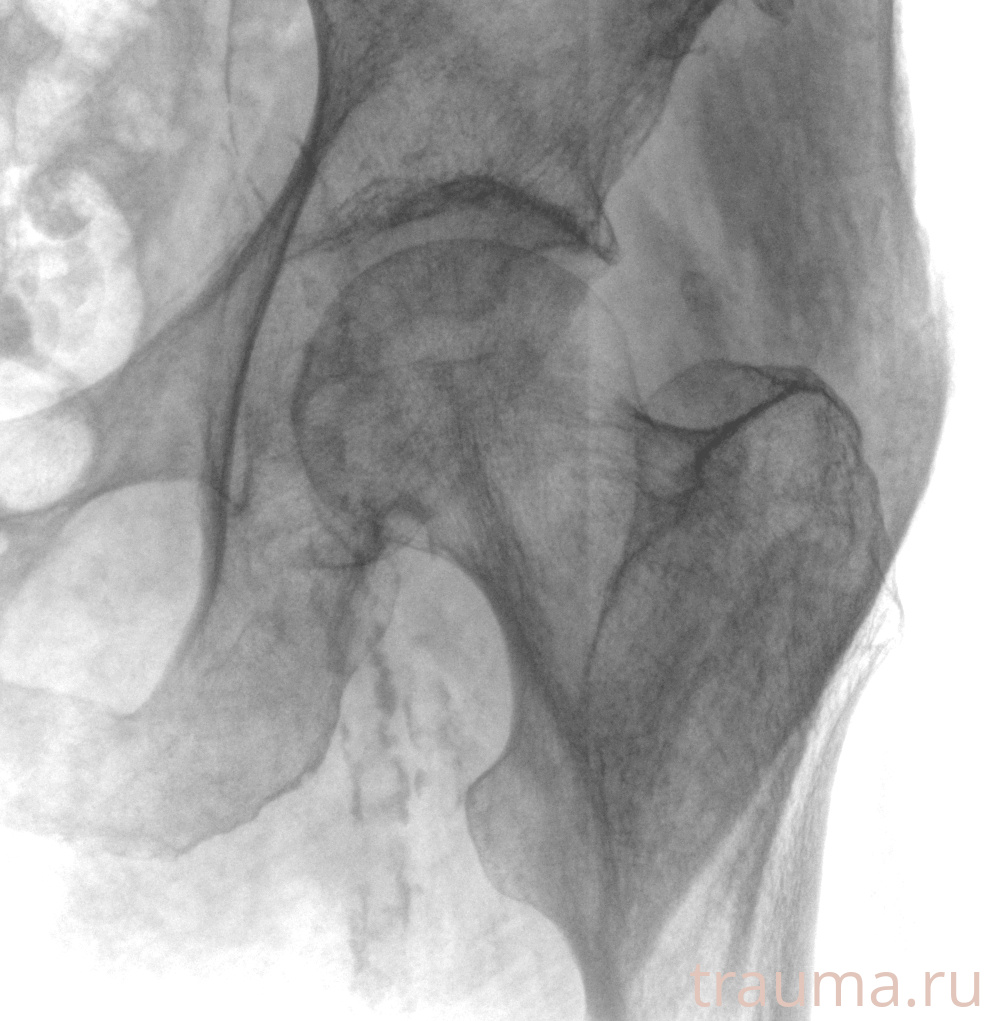

Рентгенограммы

Рентген на дому: по вашему адресу приезжает врач-рентгенолог, травматолог-ортопед с мобильным рентгеновским аппаратом, проводит диагностику травмы или заболевания, делает необходимые рентгенограммы, дает рекомендации по дальнейшему лечению. Получить качественные снимки в домашних условиях возможно благодаря уникальной методике, разработанной МосРентген Центром для института  Склифосовского